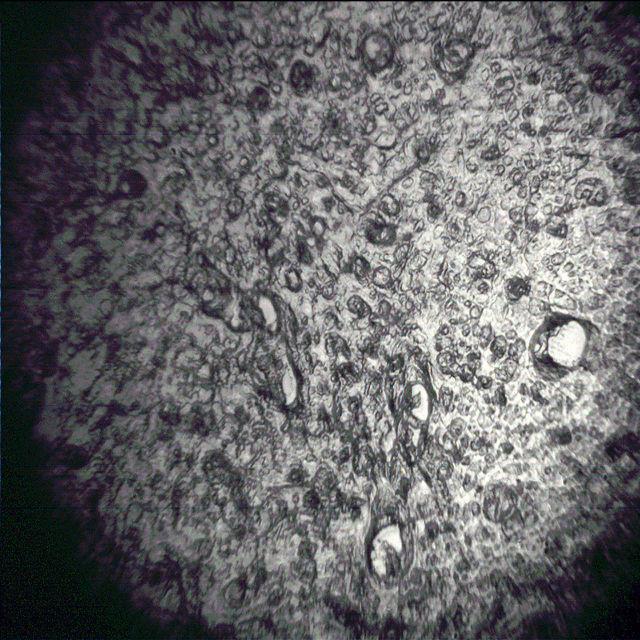

Фотография среза мозга мыши

Фотография экспериментальной установки

Кроме того, задача второго года заключалась в том, чтобы приблизиться к самим практическим применениям. В качестве объектов, от которых научный коллектив планирует получить сигнал, в первую очередь, выбраны выращенные клетки и срезы мозга мыши. С помощью созданного прототипа микроскопа учёные совместно с коллегами из Института молекулярной и клеточной биологии СО РАН смогут исследовать структуру образцов и определить корреляции с психологическими отклонениями у разных особей этого вида.